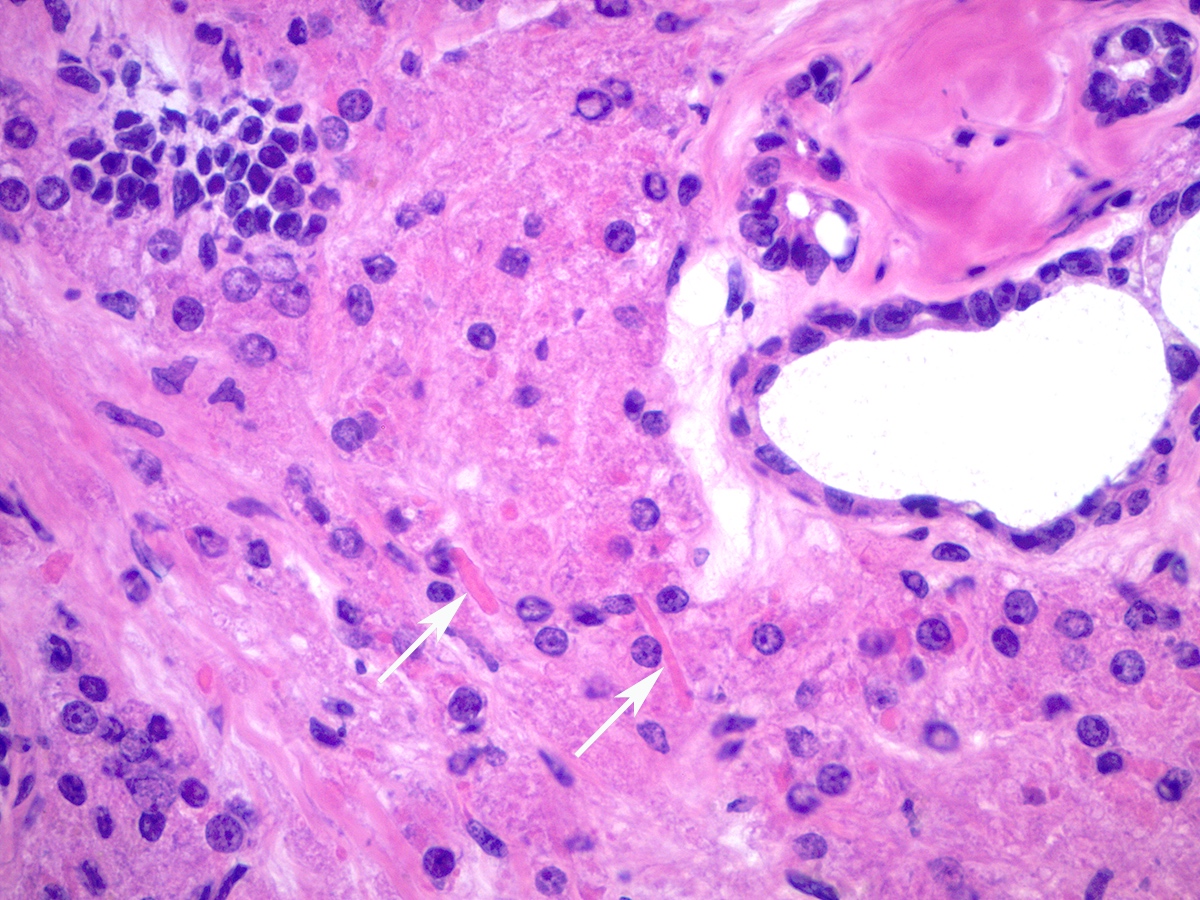

Frozen section description

- Key microscopic features on frozen section include admixture of Sertoli cell tubules or compressed cords with variable amount of Leydig cell clusters

- Intracytoplasmic Reinke crystals may be better preserved compared to formalin fixed paraffin embedded permanent sections

Microscopic (histologic) description

- Leydig cells can be recognized by their round nuclei and abundant eosinophilic cytoplasm with characteristic Reinke crystals and lipofuscin pigment

Microscopic (histologic) images